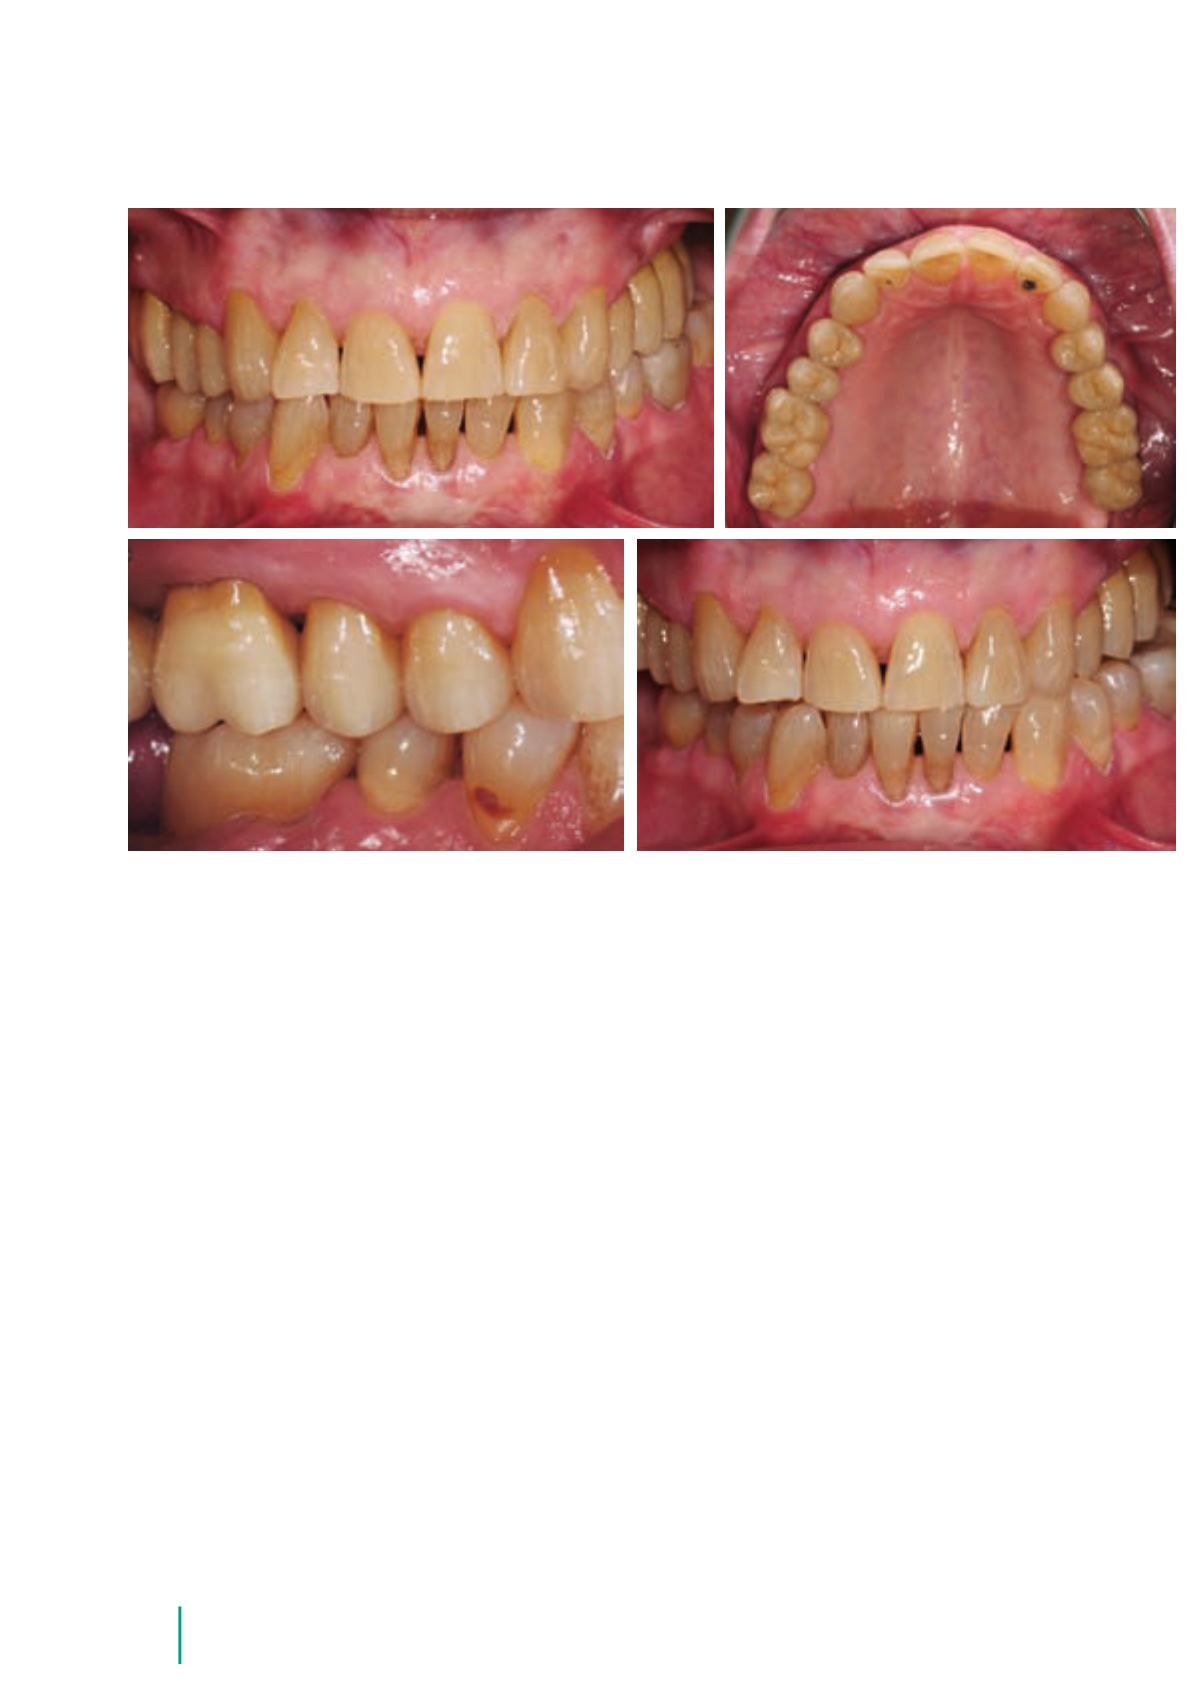

Abb. 53 bis 59

Fertige Arbeit

im Mund der Patientin

Abb. 55

Abb. 56

Abb. 54

Abb. 53